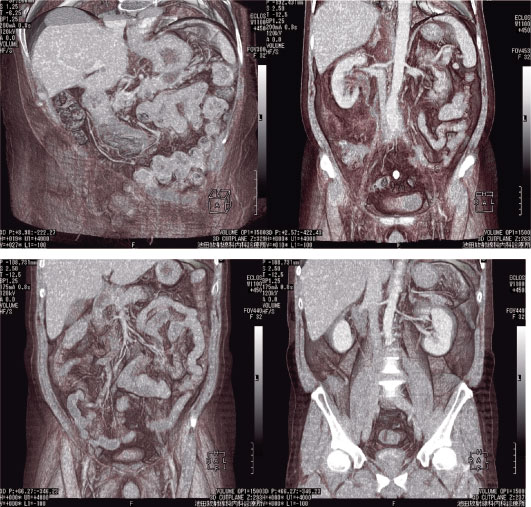

画像 3 上段左は膵体部の嚢胞性病変。右は右水腎症及び後腹膜線維症疑い。

下段左右は同一症例で上行結腸憩室炎及び背側を上行する虫垂をとらえたもの。

Voxel transmission法で処理後前腹壁から切削。